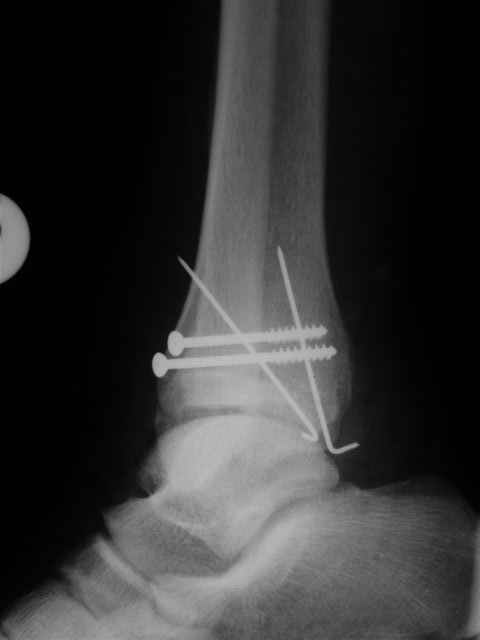

Уважаемый Иван,

Я предупреждал, что ничего сверхъестественного. Каюсь, что одна из спиц прошла несколько дальше, чем нужно было, но главное - перелом стабилизирован и больной работает суставом в полном объёме, несмотря на представленную раннее травму коленного сустава.